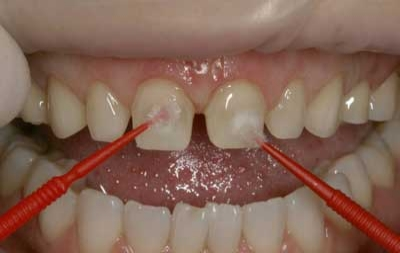

- Recently, devices became available that perforate the cortical bone with a needle that rotates in a slow-speedhand piece. A 31-gauge needle is then threaded into this hole and local anesthetic is injected into the medullary space (Figs. 1, 2).

- Remove the perforator and thread a 31-gauge needle into this hole (Fig 4).